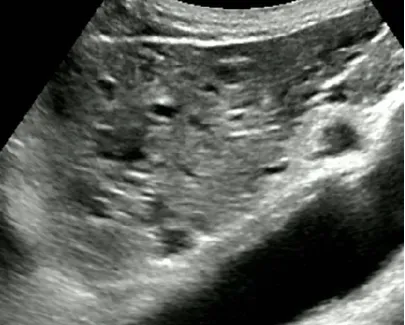

● 结节型:癌结节可单发或多个,直径约1.0~5.0cm不等。可为多中心或肝内转移所致,可伴有肝硬化。

● 弥漫型:较罕见,癌结节大小如绿豆至黄豆不等,其数目众多,弥漫分布于全肝,病程进展迅速,预后极差。

超声表现

● 结节型:肿瘤直径多在3~5cm,单发或多发

不均匀高回声或低回声为主,与周围肝组织分界较清,外周常有低回声的声晕

常合并肝硬化或慢性肝病史

● 弥漫型:弥漫散布于整个肝脏,直径在1.0cm左右,肝脏形态失常。

以不均匀低回声多见浸润生长,边界不清,外周一般无声晕或包膜回声。

常伴有肝硬化,与再生结节较难鉴别。

● CDFI:大多数为富血供肿瘤。

肿瘤区域内有丰富的彩色血流信号。

高速、高阻。